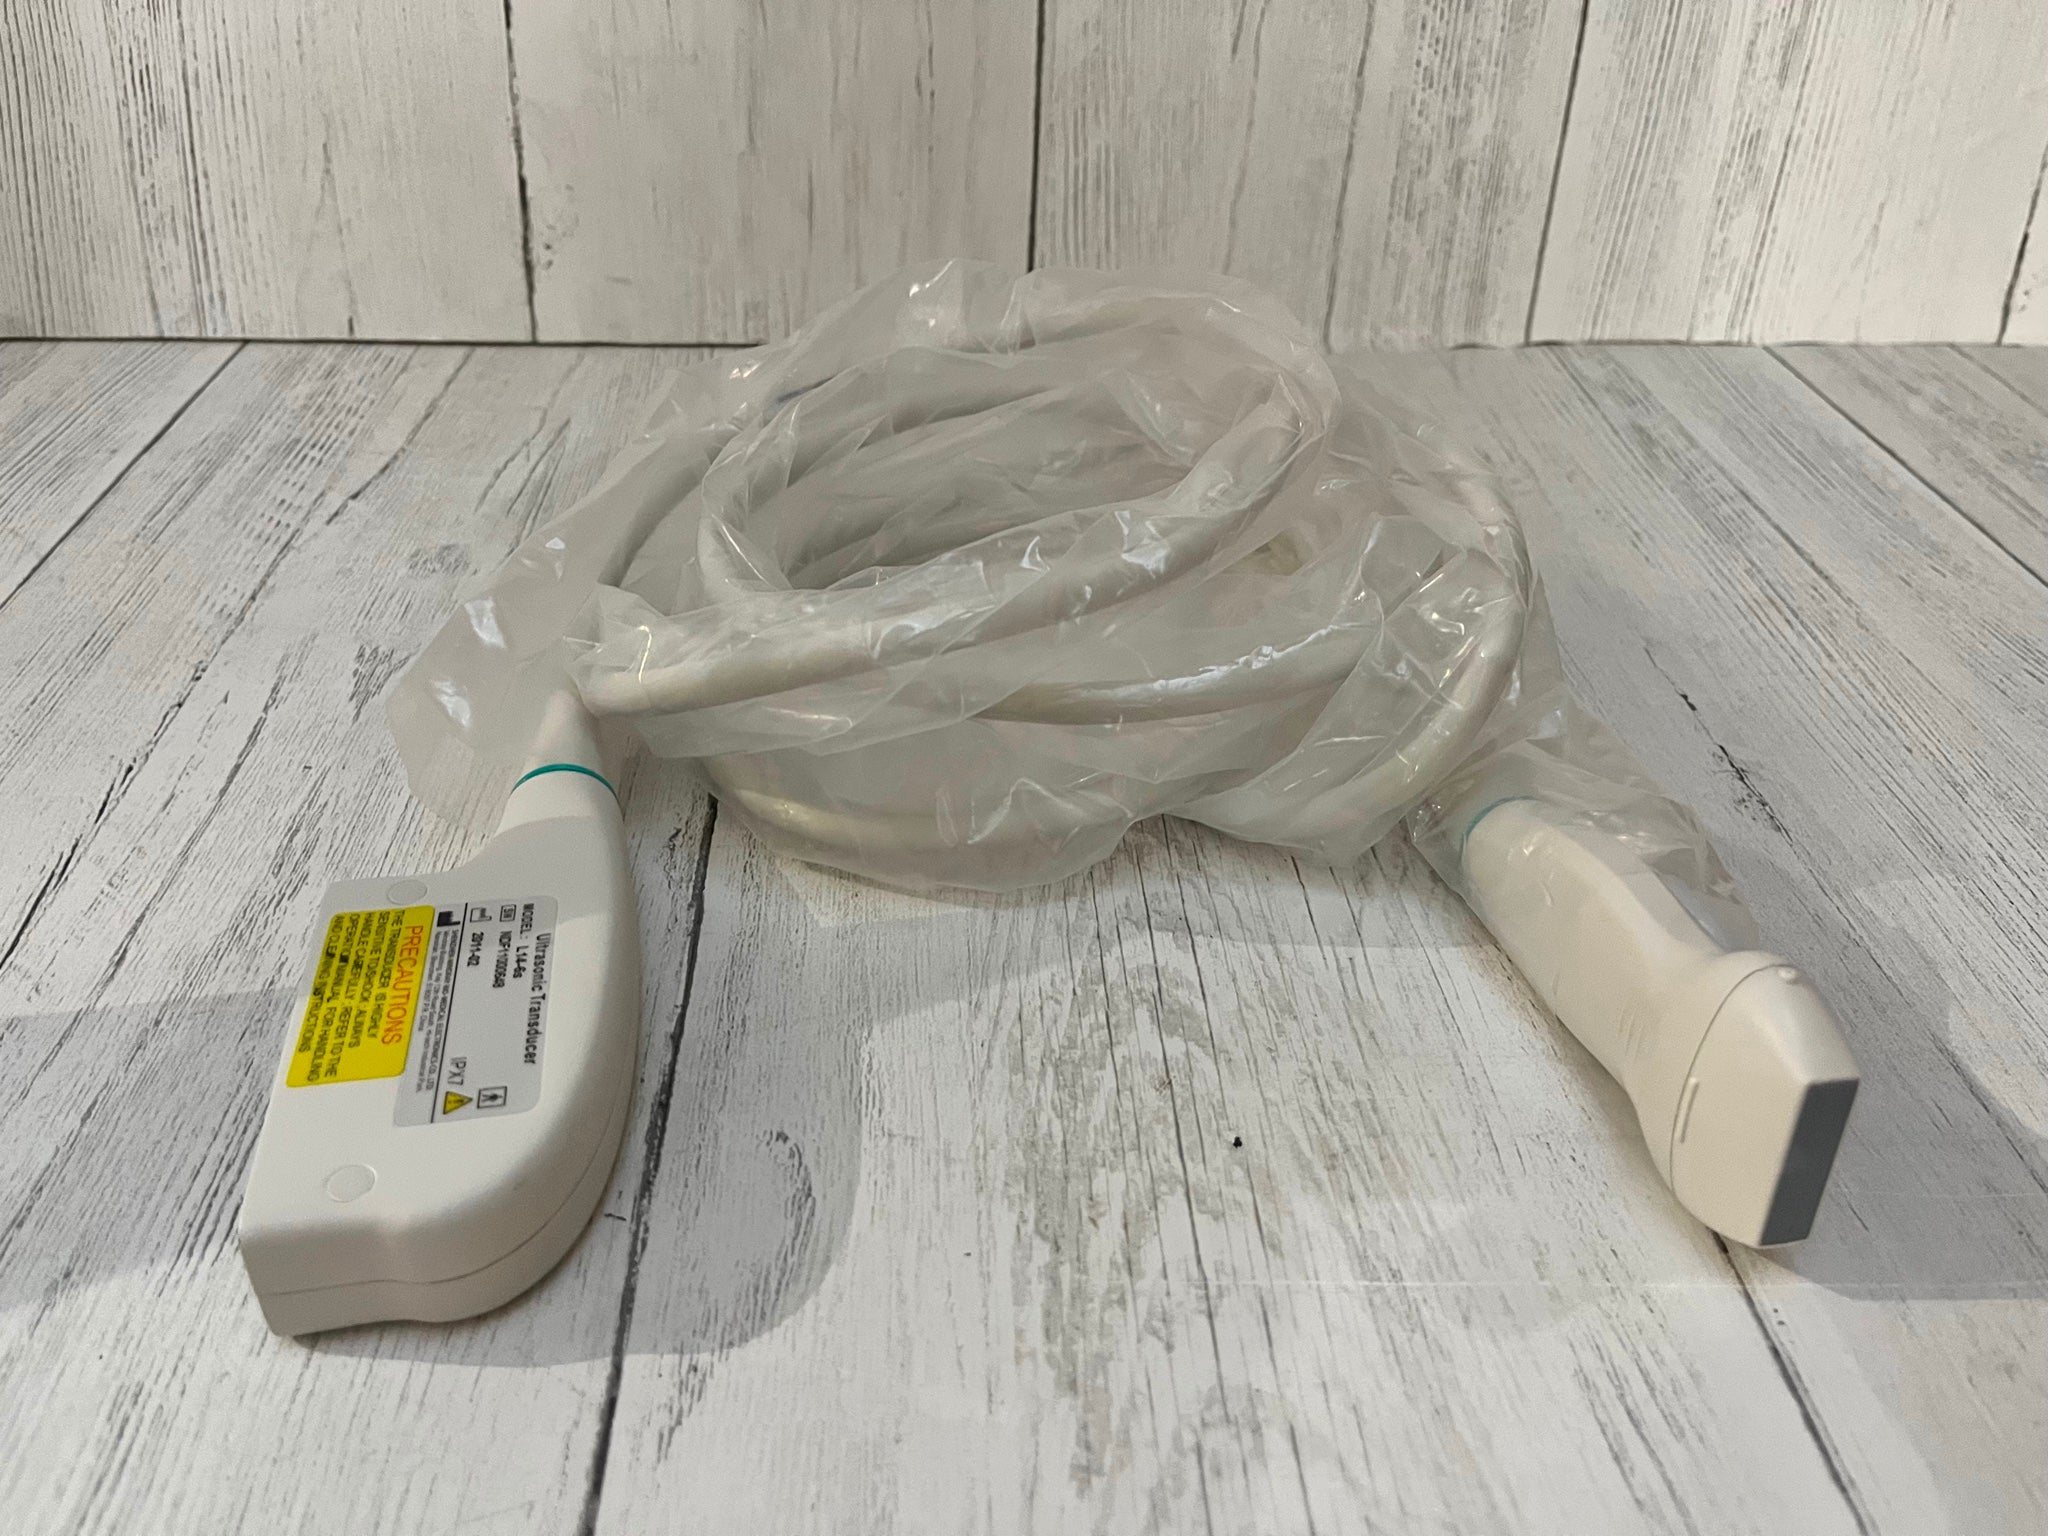

Probe Function: 3.5MHZ convex, abdominal organs

Probe 2: 7.5MHZ Transvaginal probe:gynecologic examination

This ultrasound scanner's dual probe system means that healthcare providers can easily switch between imaging modes. The convex probe is excellent for abdominal and fetal imaging, while the transvaginal probe allows for detailed pelvic examinations. Because of this flexibility, medical professionals can perform a wide variety of procedures without needing multiple machines. Therefore, hospitals can optimize their workflow and save valuable time.